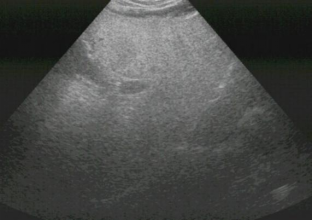

正常的肝在超声图像中呈现出均匀的低回声(类似灰黑色),就像一块质地细腻的绸缎,内部的门静脉、肝静脉等血管结构清晰可辨,走行自然流畅。而脂肪肝则截然不同:由于肝细胞内堆积了过量脂肪(主要是甘油三酯),超声波遇到脂肪颗粒时反射增强,肝在图像上会显得更亮高回声,医学上称为“肝回声增强”。

严重的脂肪肝患者,肝内部的血管结构会变得模糊不清,就像隔着一层厚厚的油雾观察,连肝静脉的分支都难以辨认。通过这种 “回声增强” 和 “血管模糊” 的特征,超声能快速筛查出脂肪肝的存在。

正常肝超声图

脂肪肝超声图

重度脂肪肝:回声显著增强,血管几乎无法辨认,甚至肝深部的回声会出现衰减。